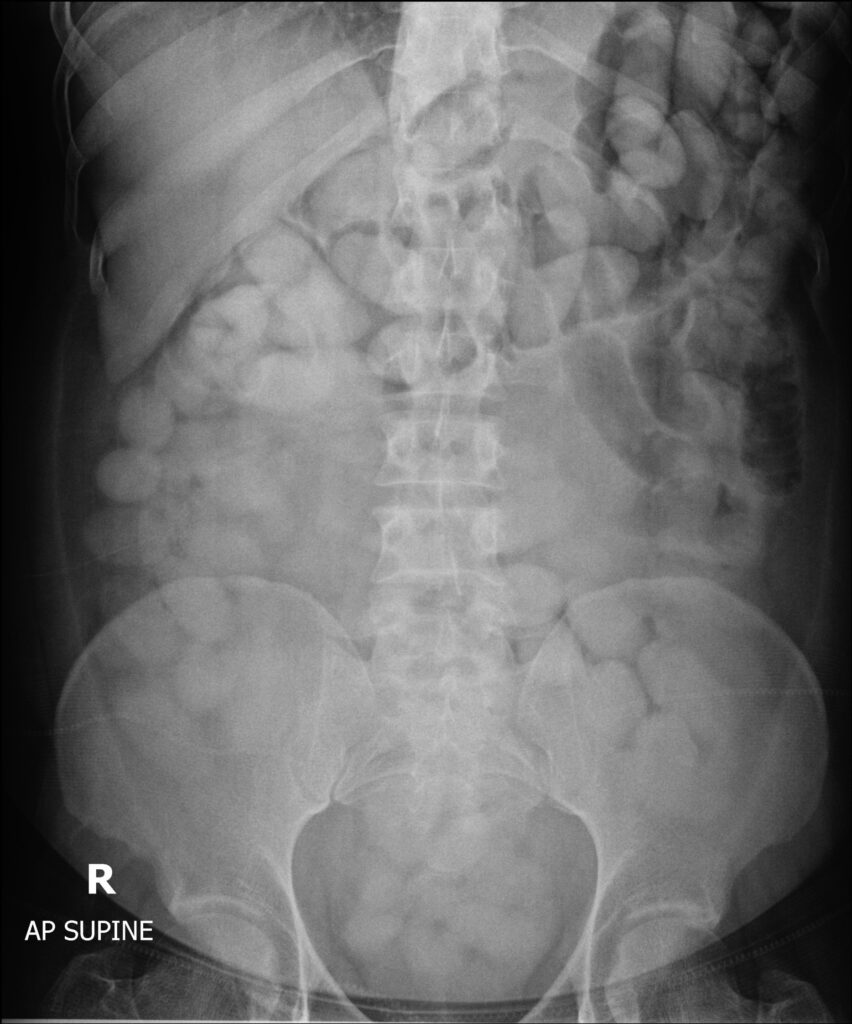

มิถุนายน 2565 เวลาประมาณ 12.30 น. ผลการตรวจคันสัมภาระไม่พบสิ่งผิดกฎหมาย แต่พบว่ามีข้อพิรุธที่อาจจะลักลอบกลืนยาเสพติด จึงนำตัวไปโรงพยาบาลถลาง จังหวัดภูเก็ต เพื่อเอกซเรย์ร่างกาย

จากการตรวจสอบภาพเอกซเรย์ พบสิ่งแปลกปลอมจำนวนมาก รูปร่างทรงกลม และทรงรีในช่องท้อง ผู้ต้องหายอมรับว่าตนได้กลืนยาเสพติด (ไม่ทราบชนิด) เจ้าหน้าที่ฯ จึงได้นำตัวผู้ต้องหาไปยังด่านศุลกากรท่าอากาศยานภูเก็ต เพื่อนำสิ่งแปลกปลอมดังกล่าวออกมาจากร่างกาย ผลการตรวจสอบสิ่งแปลกปลอมดังกล่าว พบเป็นยาเสพติตให้โทษประเภท 2 โคคาอีน จำนวนรวม 115 ก้อน น้ำหนักรวมสิ่งห่อหุ้ม 1.49 กิโลกรัม มูลค่า 4.47 ล้านบาท เป็นความผิดตามมาตรา 242 มาตรา 252 ประกอบมาตรา 166 และมาตรา 167 แห่งพระราชบัญญัติศุลกากร พ.ศ. 2560 ทั้งนั้ ด่านศุลกากรท่าอากาศยานฎเก็ต ได้นำผู้ต้องหาพร้อมของกลางส่งพนักงานสอบสวน สถานีตำรวจภูธรสาคู เพื่อดำเนินคดีตามกฎหมายต่อไป